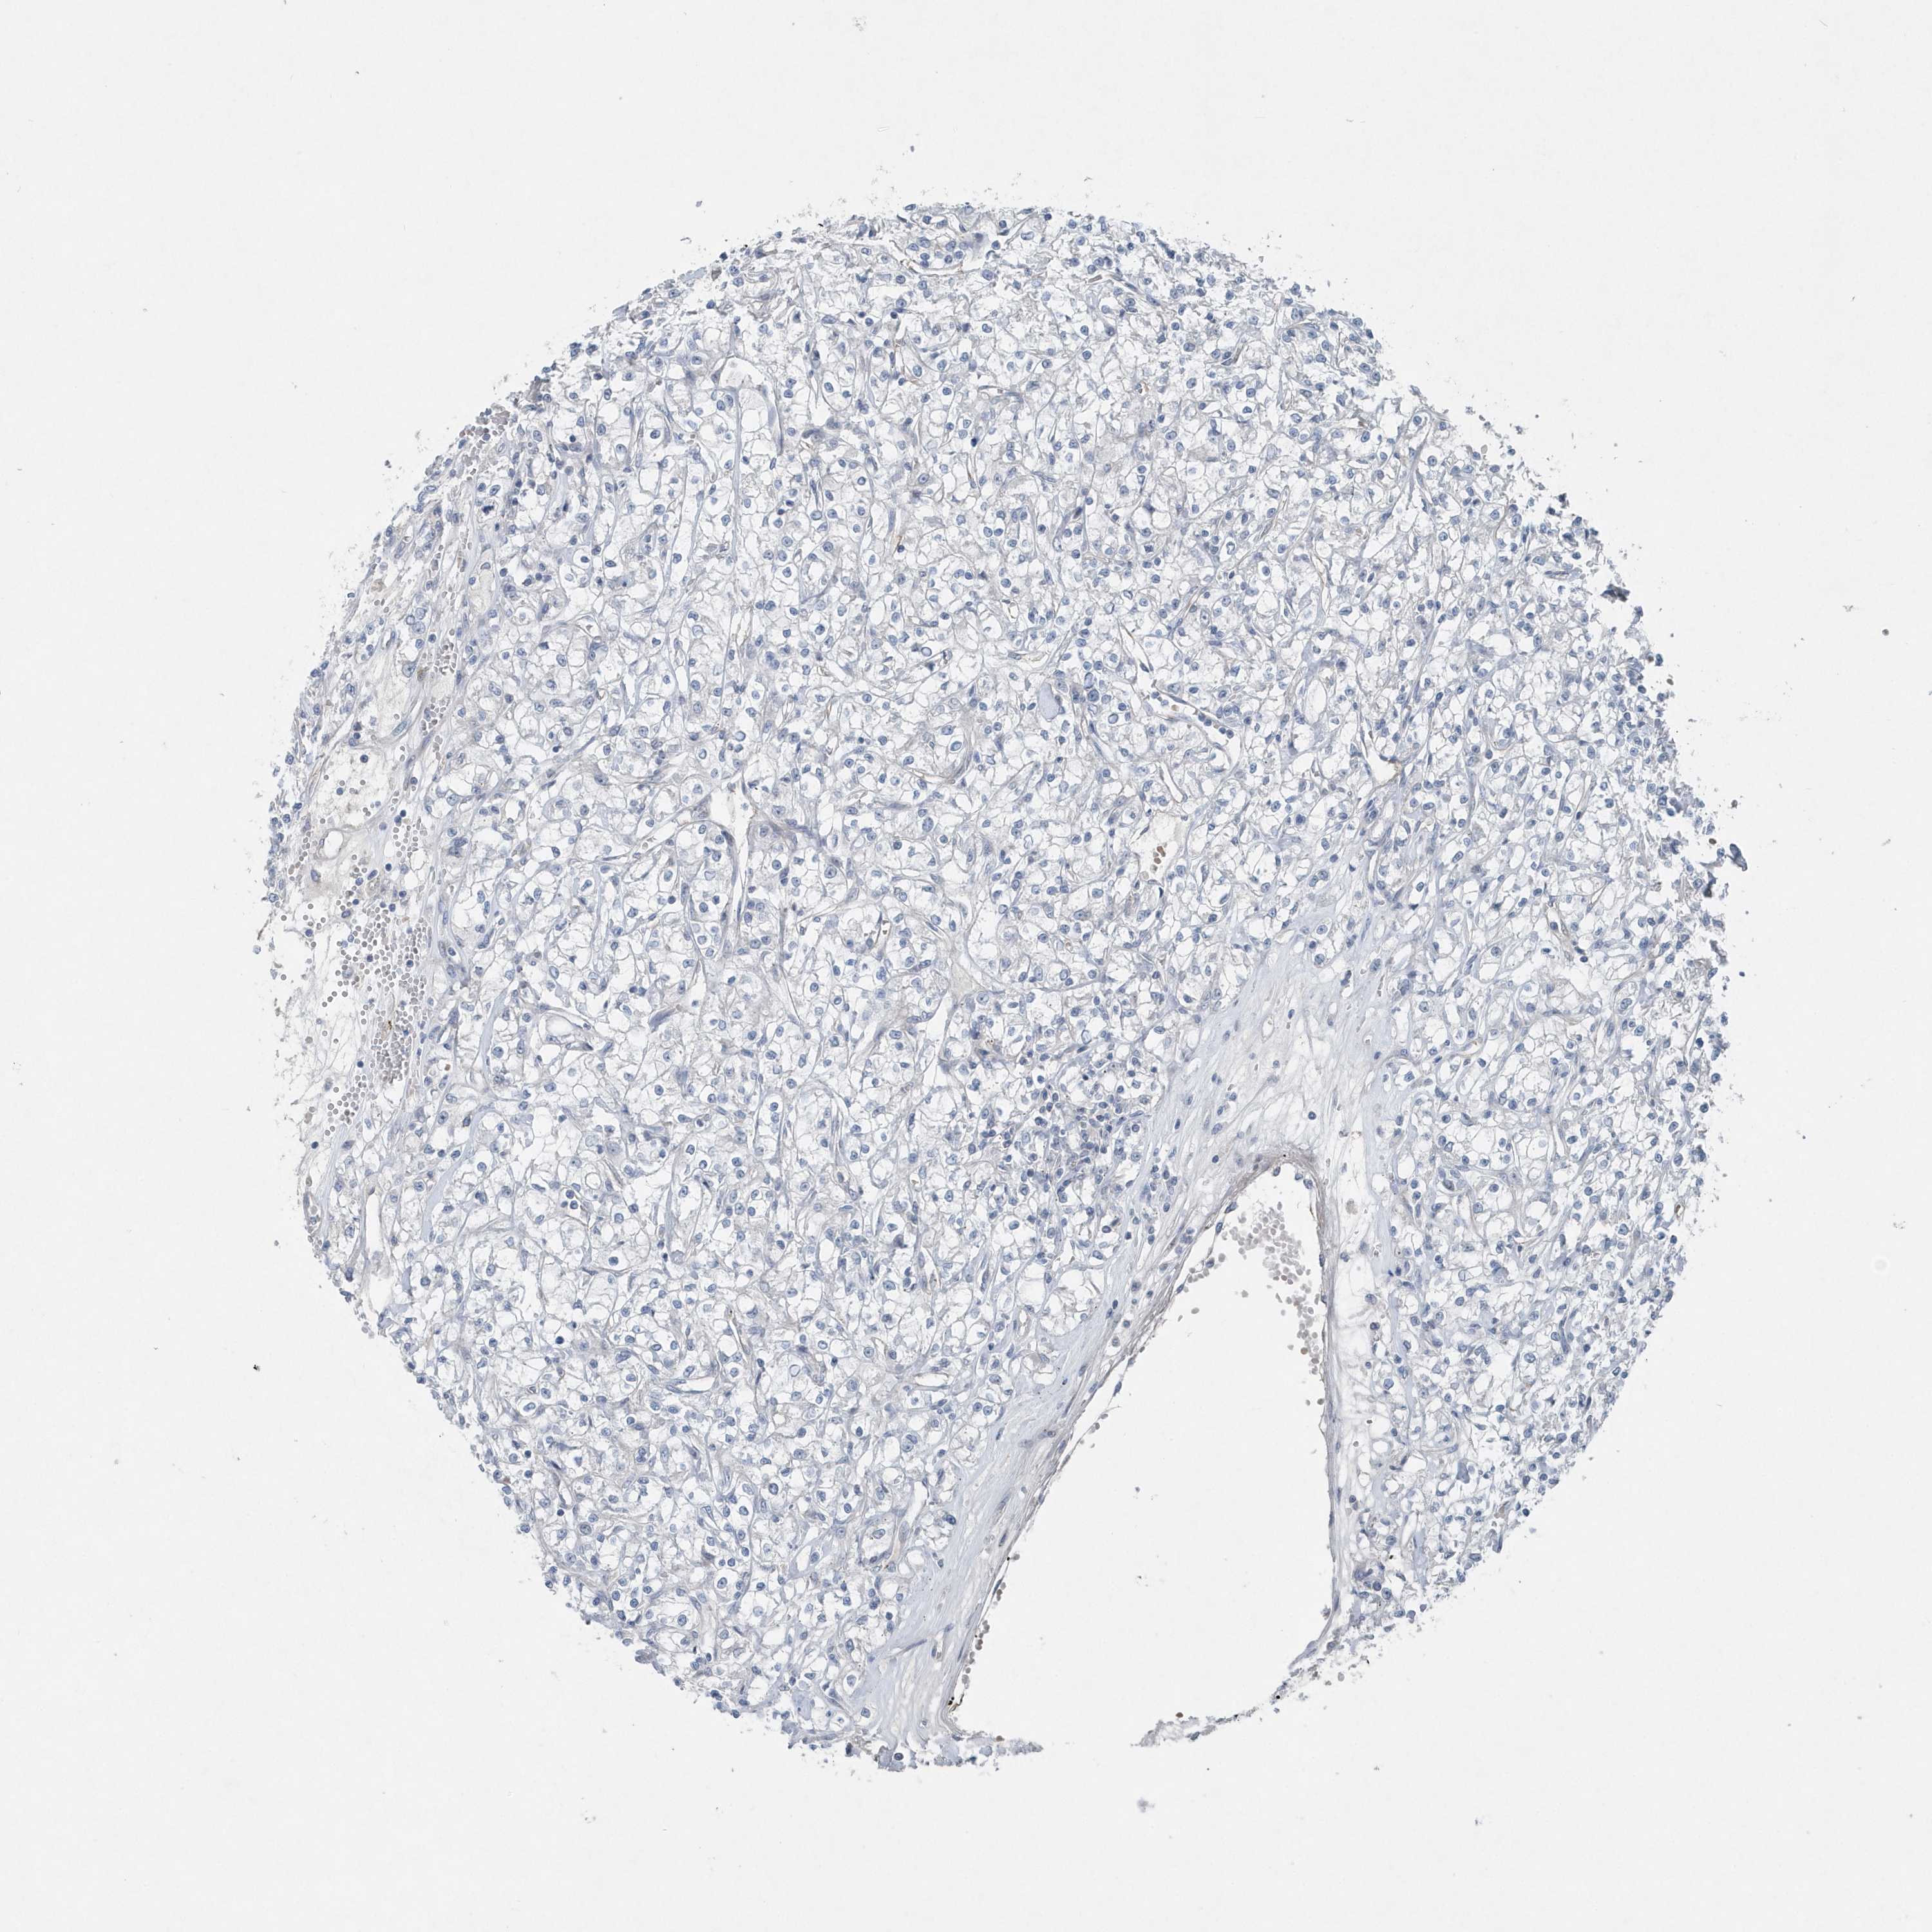

KIDNEY RENAL CLEAR CELL CARCINOMA (VALIDATION) - Interactive survival scatter ploti

The Survival Scatter plot shows the clinical status (i.e. dead or alive) for all individuals in the patient cohort, based on the same data that underlies the corresponding Kaplan-Meier plots. Patients that are alive at last time for follow-up are shown in blue and patients who have died during the study are shown in red.

The x-axis shows the expression levels (FPKM) of the investigated gene in the tumor tissue at the time of diagnosis. The y-axis shows the follow-up time after diagnosis (years). Both axes are complimented with kernel density curves demonstrating the data density over the axes. The top density plot shows the expression levels (FPKM) distribution among dead (red) and alive patients (blue). The right density plot shows the data density of the survived years of dead patients with high and low expression levels respectively, stratified using the cutoff indicated by the vertical dashed line through the Survival Scatter plot. This cutoff is automatically defined based on the FPKM cutoff that minimizes the p-score. The cutoff can be changed by dragging the vertical line or by entering a cutoff value in the square labeled "Current cut-off".

Under the Survival Scatter plot the p-score landscape (black curve; left axis) is shown together with dead median separation (red curve; right axis). Dead median separation is the difference in median mRNA expression between patients who have died with high and low expression, respectively. It is calculated as follows: median FPKM expression of dead patients with high expression - median FPKM expression of dead patients with low expression. This is intended to aid the user in visually exploring custom cutoffs and the associated p-scores and dead median separation.

Individual patient data is displayed and can be filtered by clicking on one or more of the category buttons on the top of the page. Categories describing expression level and patient information include: high, low, alive, dead, female, male and tumor stages. The scale of the x-axis can be toggled between linear and log-scale by clicking on the "x log" button. Mouse-over function shows TCGA ID, patient information and mRNA expression (FPKM) for each patient.

& Survival analysisi

Kaplan-Meier plots summarize results from analysis of correlation between mRNA expression level and patient survival. Patients were divided based on level of expression into one of the two groups "low" (under cut off) or "high" (over cut off). X-axis shows time for survival (years) and y-axis shows the probability of survival, where 1.0 corresponds to 100 percent.

MCC is validated prognostic, high expression is favorable in Kidney Renal Clear Cell Carcinoma (validation)

Best expression cut offi

Based on the FPKM value of each gene, patients were classified into two groups and association between prognosis (survival) and gene expression (FPKM) was examined. The best expression cut-off refers the FPKM value that yields maximal difference with regard to survival between the two groups at the lowest log-rank P-value. Best expression cut-off was selected based on survival analysis .

When clicking on this number, the vertical dashed line indicating cut-off, the interactive survival plot, and the Kaplan-Meier curve will be adjusted to show results based on the best expression cut-off.

: 6.25

TCGA RNA samplesi

RNA-seq data is reported as average FPKM (number Fragments Per Kilobase of exon per Million reads), generated by the The Cancer Genome Atlas (TCGA) .

Normal distribution across the dataset is visualized with box plots, shown as median and 25th and 75th percentiles. Points are displayed as outliers if they are above or below 1.5 times the interquartile range. FPKM values of the individual samples are presented next to the box plot.

Average pTPM 7.6

Number of samples 100